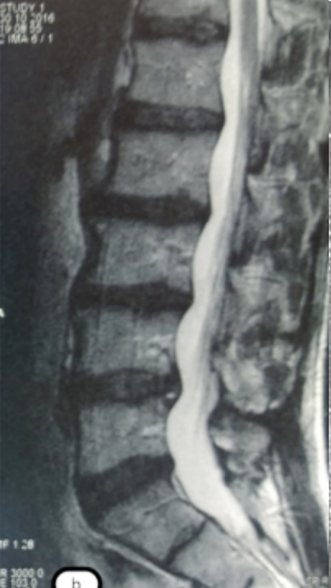

Грыжа Диска L4-L5

3 процедуры ФДТ, 9 процедур MBST

Спондилодисцит L3 – L4

4 процедуры ФДТ, 9 процедур MBST, 20 процедур ИПМТ